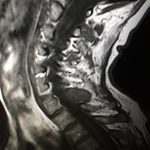

Εικόνα 3: Μαγνητική Τομογραφία (31.10.2018) Αυχενικής Μοίρας Σπονδυλικής Στήλης (ΑΜΣΣ)

(α,β) Οβελιαία Λήψη – Ακολουθία Τ1 και Τ2. Παρατηρείται προσβολή των οπισθίων σπονδυλικών στοιχείων στο επίπεδο του 7ου Αυχενικού Σπονδύλου.

(γ-ε) Εγκάρσια Λήψη – Ακολουθία Τ2. Παρατηρείται η ύπαρξη νεοπλασματικής διήθησης στα οπίσθια στοιχεία του σπονδύλου, κυρίως δεξιά, χωρίς να έχει σπάσει τελείως το δεξιό πέταλο. Η σύστοιχος σπονδυλική διάρθρωση έχει προσβληθεί.